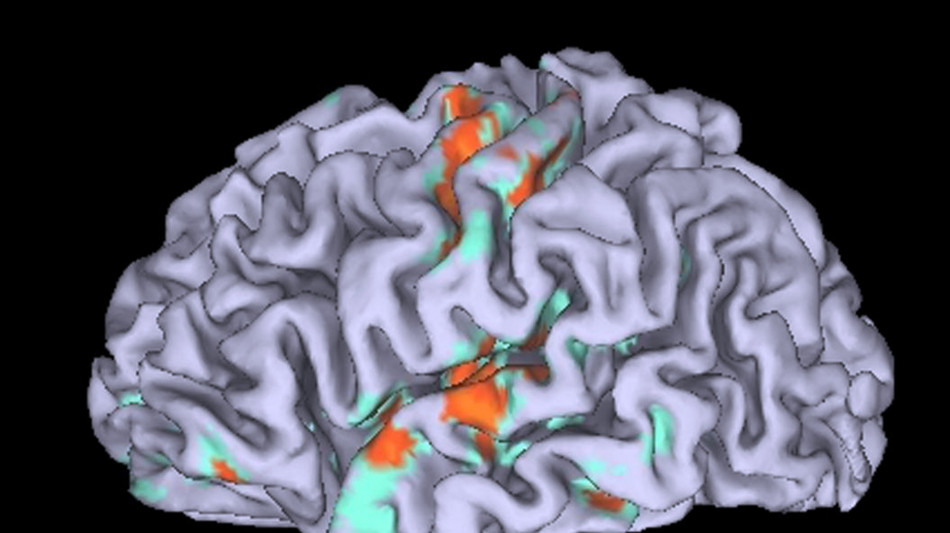

Conservatori e progressisti hanno effettivamente una diversa struttura anatomica del cervello, ma le differenze sono molto meno pronunciate di quanto si pensasse: lo dimostra uno studio condotto nei Paesi Bassi su quasi mille persone di diversa ideologia politica. I risultati sono pubblicati sulla rivista iScience da un gruppo di ricerca guidato dallo psicologo e neuroscienziato Diamantis Petropoulos Petalas dell'Università di Amsterdam. Lo studio è nato con l'obiettivo di verificare, su un campione più ampio e variegato, i risultati di una ricerca britannica del 2011 che aveva rilevato significative differenze nell'anatomia cerebrale di persone di diversa ideologia politica, soprattutto a livello dell'amigdala (che controlla la percezione del rischio) e la corteccia cingolata anteriore (coinvolta nel rilevamento degli errori, nel controllo degli impulsi e nella regolazione emotiva). I ricercatori hanno quindi preso in esame le risonanze magnetiche cerebrali di 928 individui di età compresa tra 19 e 26 anni, con un livello di istruzione e un'appartenenza politica rappresentativi della popolazione olandese. Dato che i Paesi Bassi hanno un sistema multipartitico (e non bipartitico come il Regno Unito), lo studio è stato anche in grado di confrontare le strutture cerebrali lungo tutto lo spettro politico da sinistra a destra. Inoltre, i ricercatori hanno esaminato l'ideologia dei partecipanti da vari punti di vista, tra cui la loro identità politica e la posizione sulle questioni socioeconomiche. In linea con il vecchio studio britannico, è emersa un'associazione tra conservatorismo e volume di materia grigia nell'amigdala, ma è risultata essere tre volte più debole. A differenza dello studio originale, inoltre, il team di Petropoulos non ha trovato alcuna associazione tra conservatorismo e un volume inferiore di materia grigia nella corteccia cingolata anteriore. I ricercatori hanno anche esteso la loro analisi per esaminare potenziali associazioni tra identità politica e altre regioni del cervello. In questo modo hanno scoperto un'associazione positiva tra il volume di materia grigia nel giro fusiforme destro (una regione nel lobo temporale essenziale per le funzioni visive e cognitive) e il conservatorismo economico e sociale.